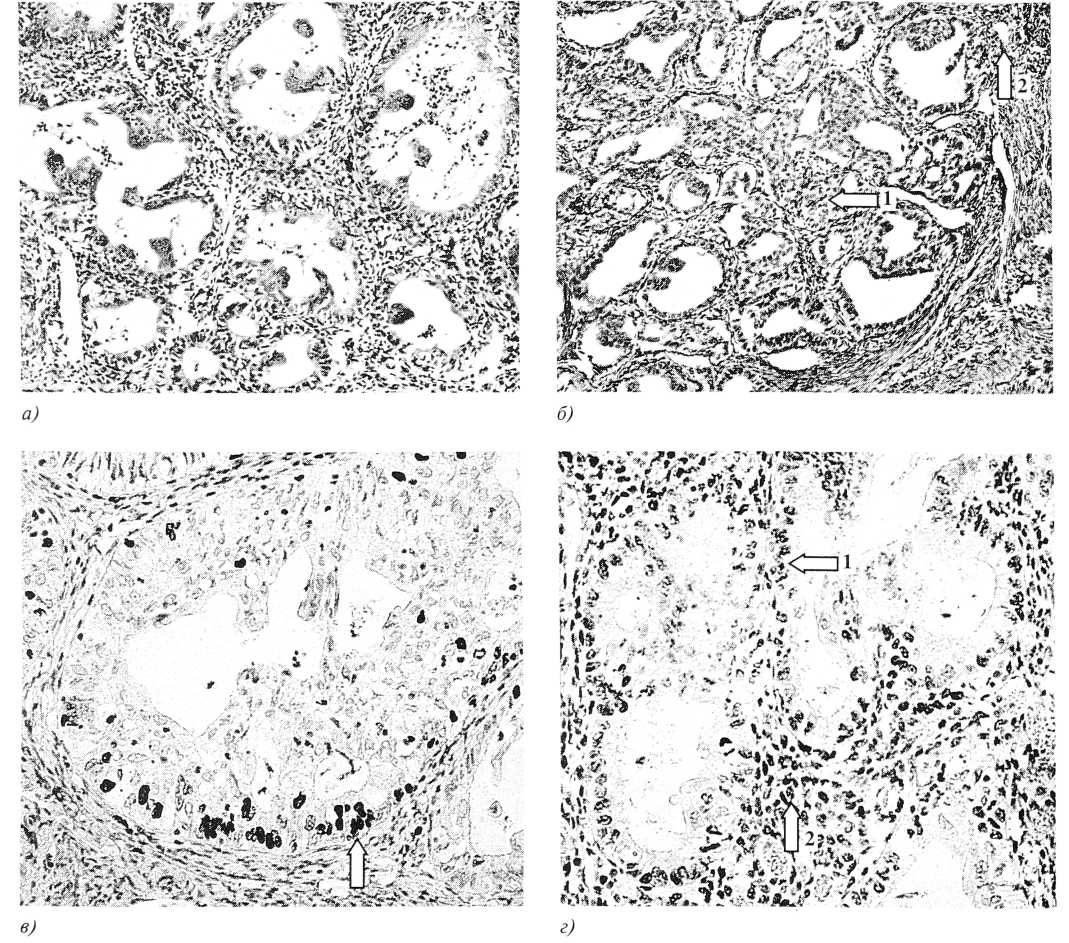

Рис. 1. Малигнизированный аденомиоз:

а — участок железисто-сосочковой аденокарциномы. Окраска гематоксилином и эозином. х200;

б — железисто-сосочковая аденокарцинома с участками солидизации (указано стрелкой 1) и началом инвазивного роста (указано стрелкой 2). Окраска гематоксилином и эозином. х180;

в — экспрессия Ki-67 в железисто-сосочковой аденокарциноме (указано стрелкой). х220;

г — рецепторы эстрогенов в эпителии (указано стрелкой 1) и в строме (указано стрелкой 2) железисто-сосочковой аденокарциномы. х200